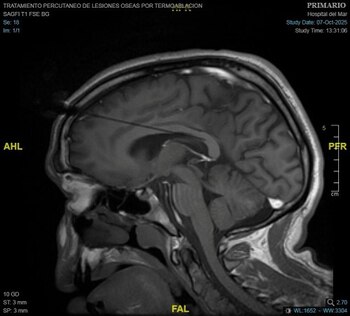

El paciente, que pasó por quirófano el pasado 7 de octubre, presentaba un tipo de epilepsia resistente al tratamiento farmacológico convencional. Al mismo tiempo, no podía ser intervenido de cirugía curativa. Tras un proceso de planificación con imágenes 3D junto al equipo de la Unidad de Epilepsia, encabezado por el Dr. Rodrigo Rocamora, se seleccionó el área del cuerpo calloso del cerebro a tratar para interrumpir la comunicación entre los dos hemisferios cerebrales. El equipo liderado por el Dr. Carlo Marras, jefe del Servicio de Neurocirugía, junto a la Dra. Nazaret Infante, médica adjunta del mismo servicio.

Según explica el hospital en un comunicado, para la realización de esta técnica "se colocan de dos a tres sondas láser a través de accesos milimétricos en el cráneo que servirán, con monitorización constante de imágenes de resonancia magnética, para realizar la intervención y obtener el resultado esperado". Así, gracias las altas temperaturas que consigue alcanzar el láser y con ayuda de un sistema robótico, se actúa sobre la zona concreta del cuerpo calloso seleccionada sin afectar las zonas del cerebro circundantes.